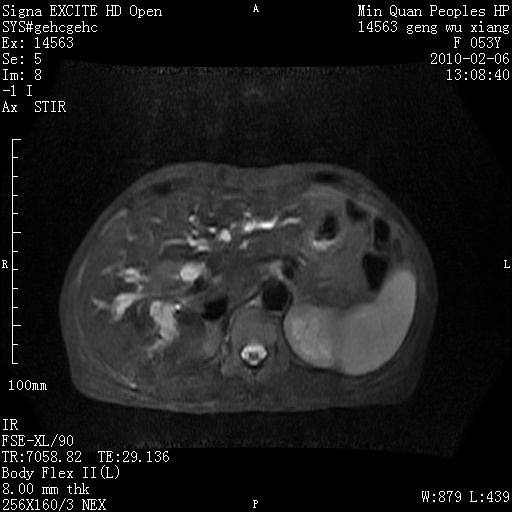

标题: MRI2762:胆道梗阻原因?

f,53y,全身黄染多日。

高位胆道梗阻 胆管癌可能性大

支持 高位胆道梗阻 胆管癌可能性大。